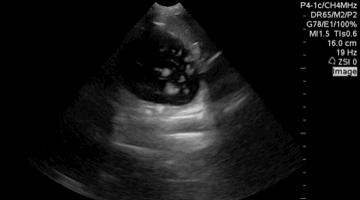

QA of the day. Foreshortened Apical 4 Chamber View. Flatten that probe #pocus #foamus #meded